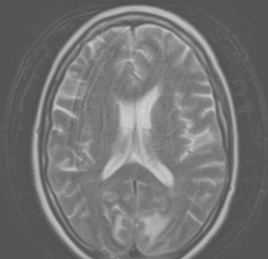

Описание клинического случая. Пациентка 63 лет с хронической артериальной гипертензией 3 ст., 3 ст., риск 4 и сахарным диабетом 2 типа планово поступила для хирургического вмешательства по поводу рака прямой кишки. Во время операции под общей анестезией у пациентки отмечалась нестабильная гемодинамика с повышением АД максимально до 160\100 мм.рт.ст.. После пробуждения пациентка отметила отсутствие зрения и нарушение координации, всё это сопровождалось неконтролируемой артериальной гипертензией с подъёмом АД максимально до 182\130 мм.рт.ст.. На МРТ в обеих затылочных долях (справа 43 мм х 26,5 мм х 40 мм) отмечались участки гиперинтенсивного сигнала в режиме Т2 без признаков ограничения диффузии, паравенктрикулярно в белом веществе головного мозга - очаги до 2 мм сосудистого генеза. Неврологические нарушения пациентке удалось купировать, зрение восстановилось в течение 2 недель.